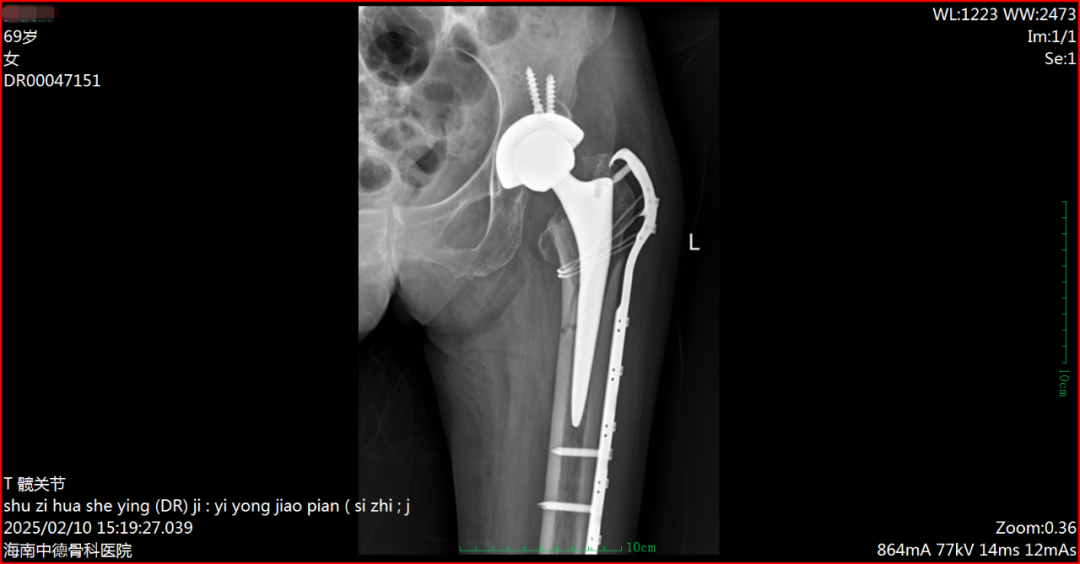

术后DR片(86岁钟阿婆)

术后DR片(69岁张阿姨)

手术团队在医疗院长兼关节外科、运动医学科主任付昆教授的指导下,在麻醉科和手术室的密切配合下,由关节外科颜约军副主任亲自主刀,牛通、游满东、陈晓渴等担任助手,成功为两位高龄老人实施了“髋关节置换术后假体周围骨折翻修内固定手术”。手术时间短,假体翻修后稳定性高,骨折对位固定好。术后,患者在骨科加速康复病房的管理下,第二天就扶助行器下地行走,现已出院。